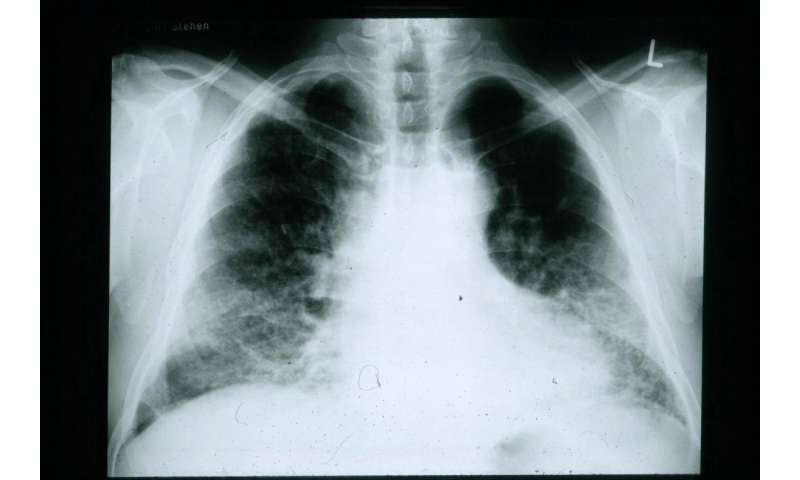

Scientists at Vanderbilt University Medical Center (VUMC) and the Translational Genomics Research Institute (TGen) in Phoenix, Arizona, have discovered previously unreported genetic and cellular changes that occur in the lungs of people with pulmonary fibrosis (PF).

PF can be triggered by inhaling coal or asbestos, exposure to radiation and certain drugs and hypersensitivity and autoimmune reactions. In addition, “idiopathic” PF, a subset of the disease with no known cause, kills up to 40,000 Americans each year, according to the Pulmonary Fibrosis Foundation.

Normally the ECM provides the structural and biochemical support between cells that are organized into tissues. But in PF and IPF, the progressive accumulation of ECM destroys the alveoli, the tiny air sacs in the lungs that allow for the exchange of oxygen and carbon dioxide.